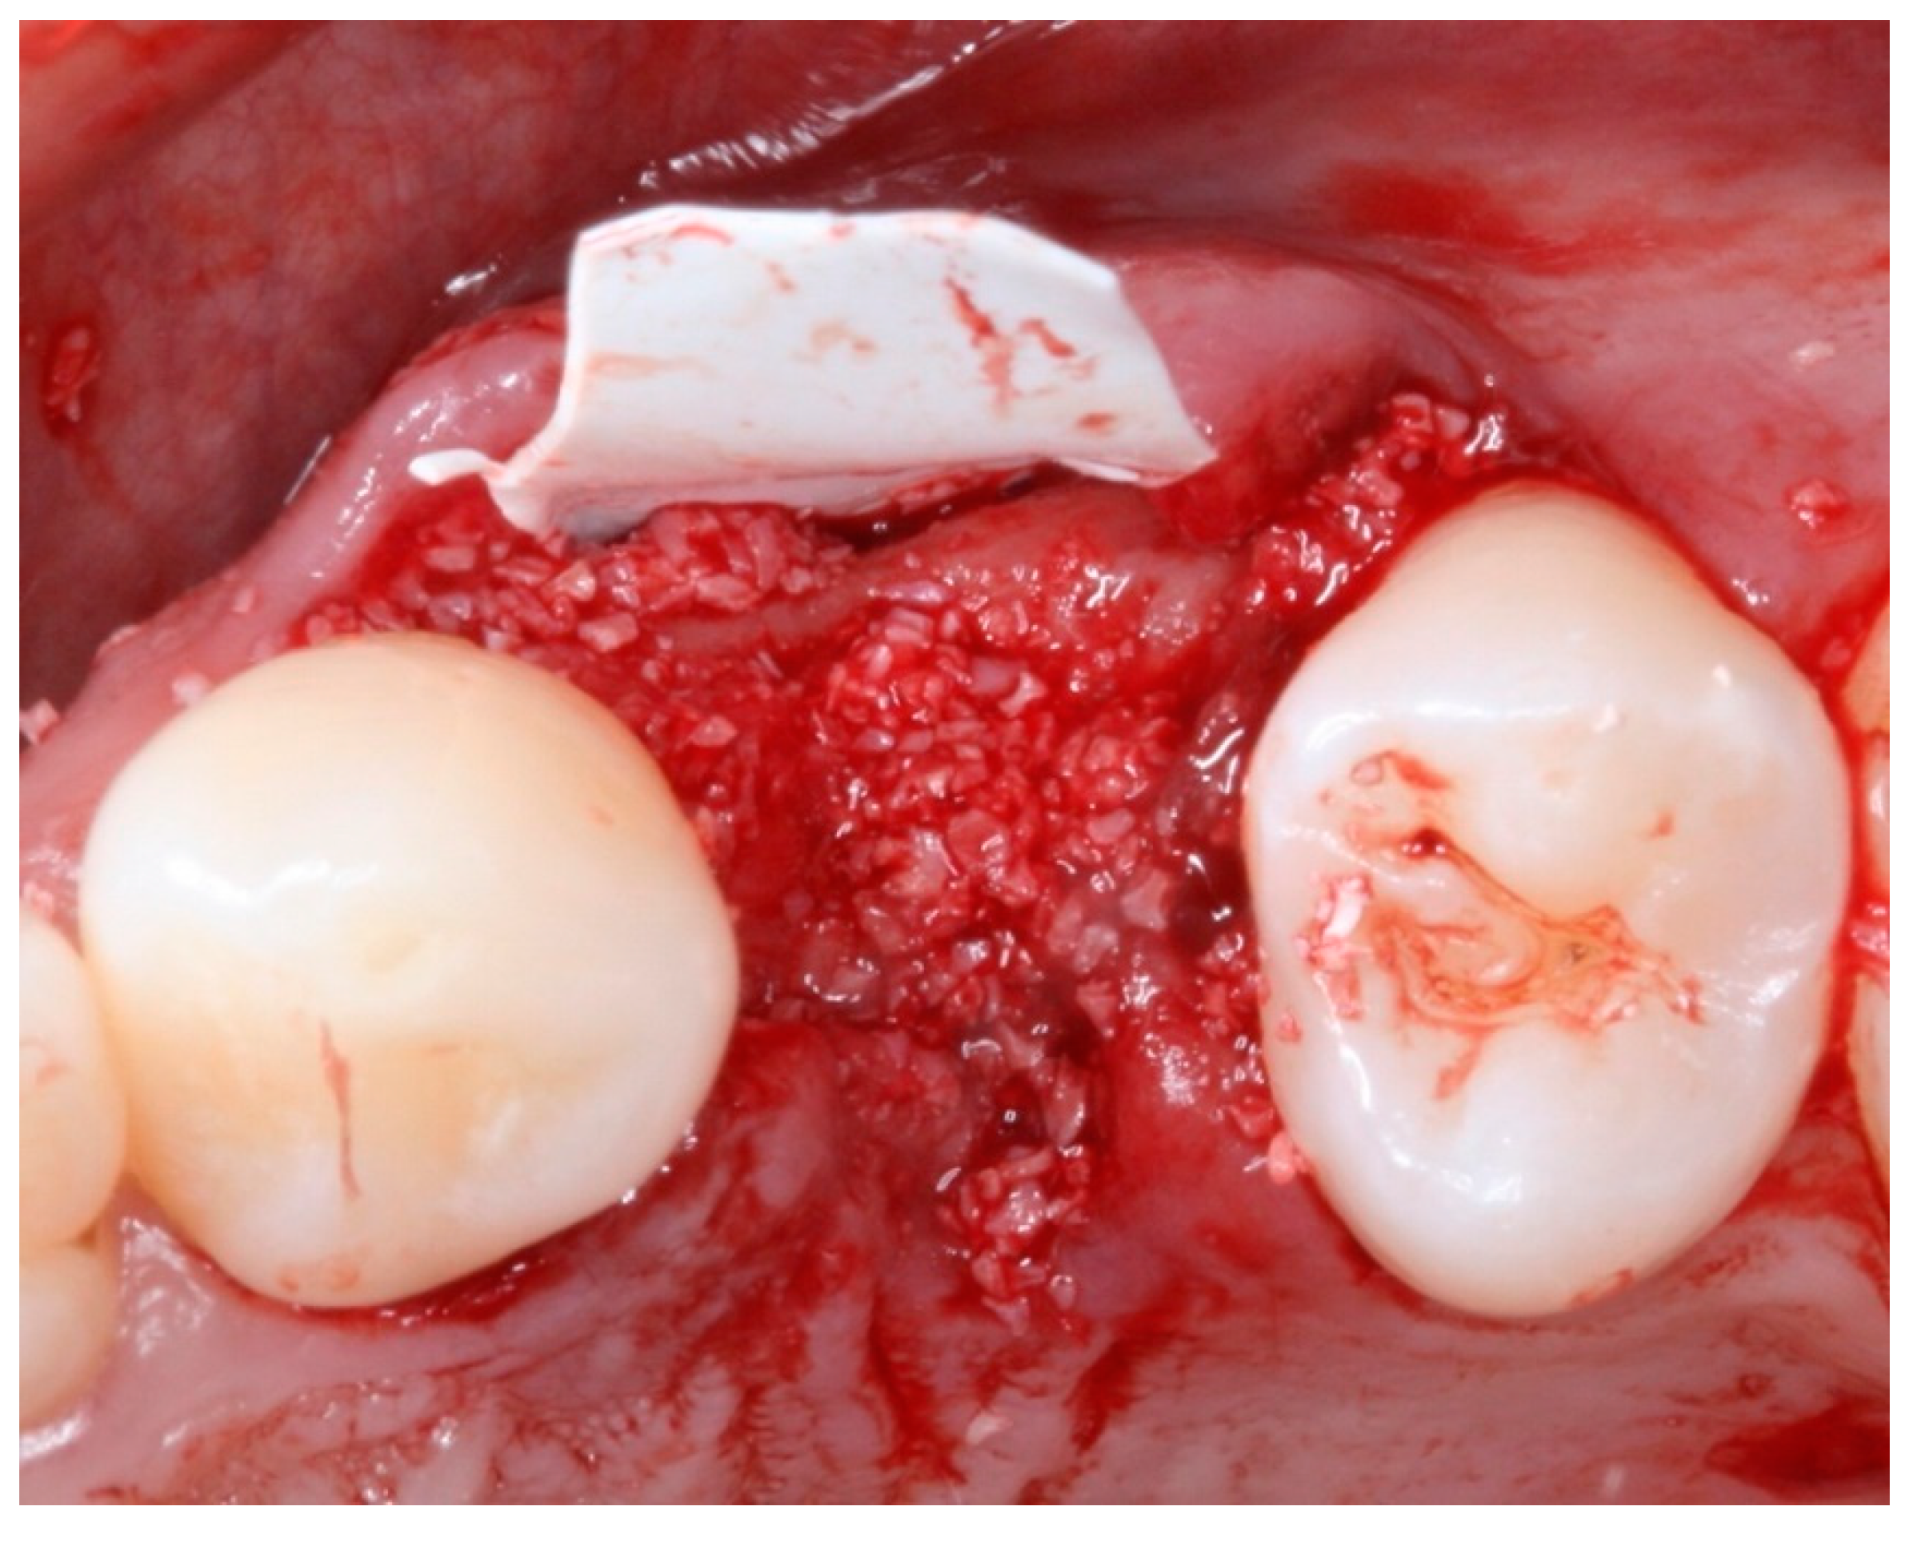

2. Materials and Methods

2.4. Groups